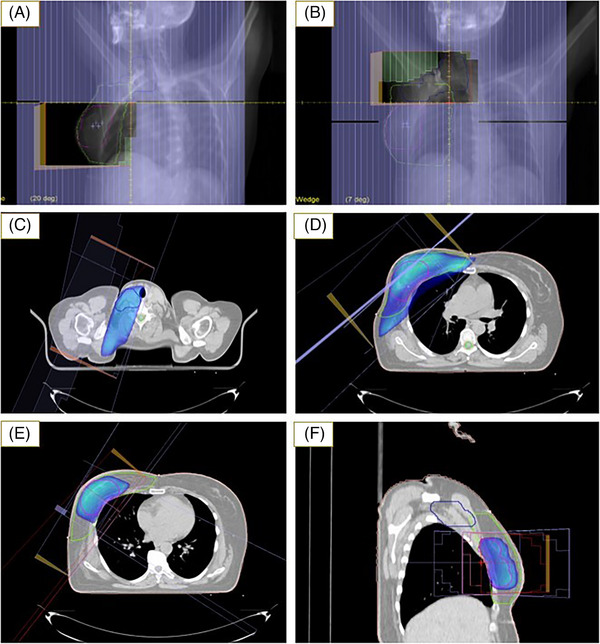

Methods: Thirty patients who underwent breast cancer surgery (BCS) with axillary lymph node dissection (ALND) were enrolled. Two plans were generated for each case: (1) dpSIB-VMAT, and (2) 3D-CRT-seqB plans. Planning target volume (PTV)-Breast and PTV-Nodes were prescribed at a dose of 50 Gy in 25 fractions in both plans. PTV-Boost was prescribed at a dose of 60 Gy in 25 fractions simultaneously in the dpSIB-VMAT plans, whereas it was planned sequentially in the 3D-CRT-seqB plans at 10 Gy in 5 fractions. Dosimetric parameters were compared between the two plans.

Abstract Image